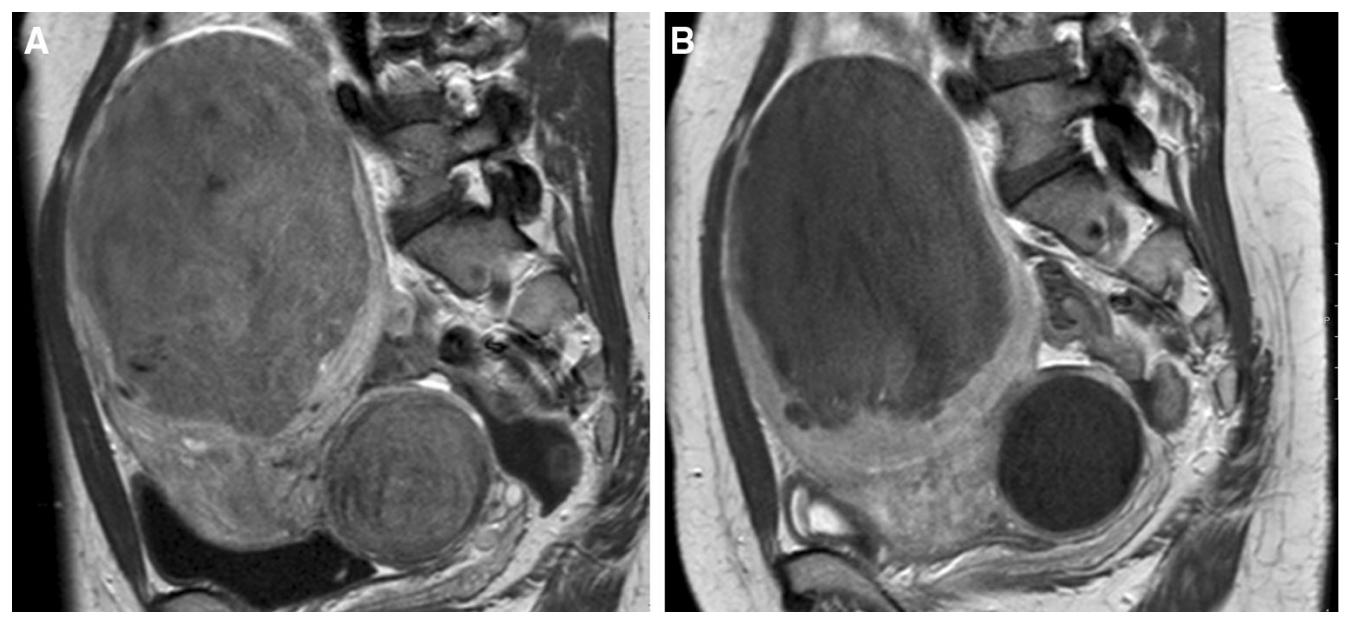

中年女性,发现子宫肌瘤进行性增大5年余。彩超提示多发、巨大子宫肌瘤,肌瘤外突明显,最大者直径近10cm。近半年尿频、尿急症状进行性加重,考虑增大的子宫肌瘤压迫膀胱所致。

- 盆腔磁共振检查显示显示多发巨大子宫肌瘤,部分突出浆膜外,明显压迫膀胱。

MRI显示多发子巨大宫肌瘤,压迫膀胱

冠状位

矢状位